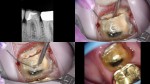

Here, traditional access would have removed most of the remaining PCD. We leveraged the caries and existing loss of tooth structure at the mesial, and poked a hole in the distal with an EG4. Chairside in the scope manages the field and NaOCl irrigation easily.

Resin mesial and distal.

With a skilled restorative dentist and technician a feather edge gold restoration is do-able…but I’m talking beyond my pay grade.

Here, the VertiPrep would probably be best as tooth structure is available 360. This will probably get a light chamfer and gold however…